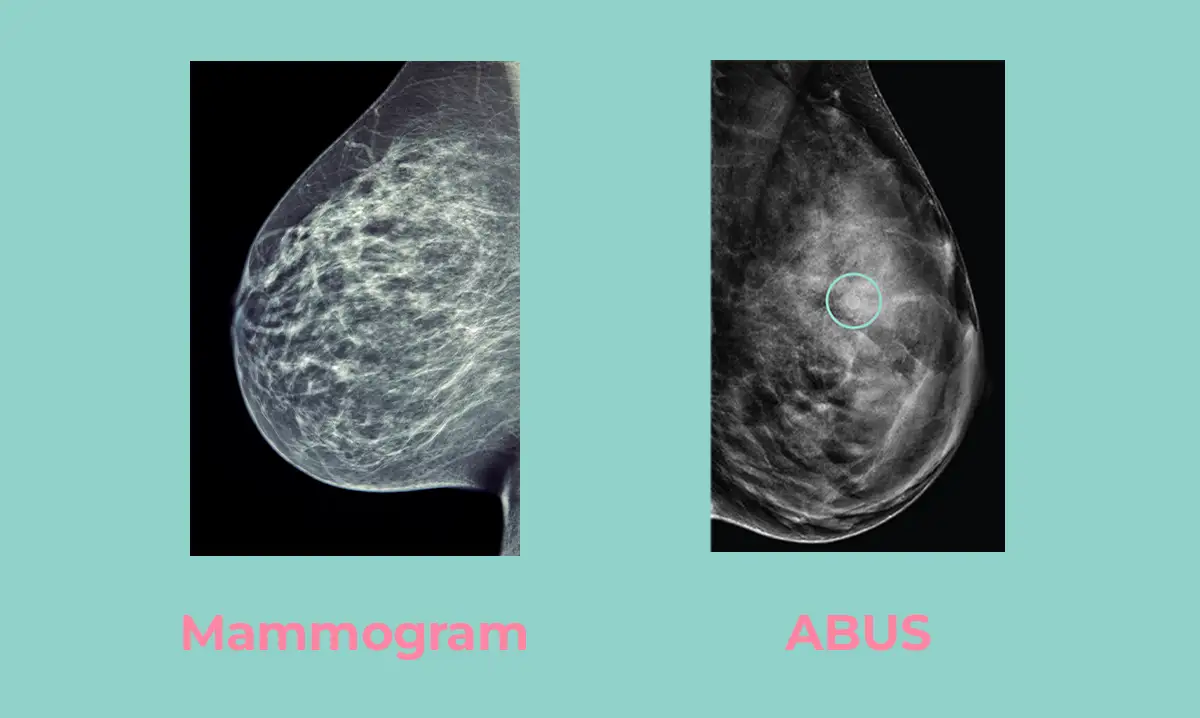

Nearly 40% of women have dense breast tissue, which can make it more challenging to detect cancer with a mammogram alone. Dense tissue and tumors both appear white on a mammogram, which can cause cancers to be hidden or missed. That’s where Automated Breast Ultrasound (ABUS) comes in. ABUS is specifically designed to improve cancer detection in women with dense breasts by providing a more transparent, complete image.

ABUS stands for Automated Breast Ultrasound System. It’s a screening tool that uses sound waves to create detailed 3D images of the breast, beneficial for women with dense breast tissue.

Nearly 40% of women have dense breast tissue, which can make it harder to detect cancer with a mammogram alone. ABUS provides a clearer view, increasing the chance of finding cancer early.

However, ABUS is only a complement to mammograms. Mammograms remain the gold standard for early detection, as they provide a comprehensive view of the breast area and can detect specific cancers that ultrasound cannot.